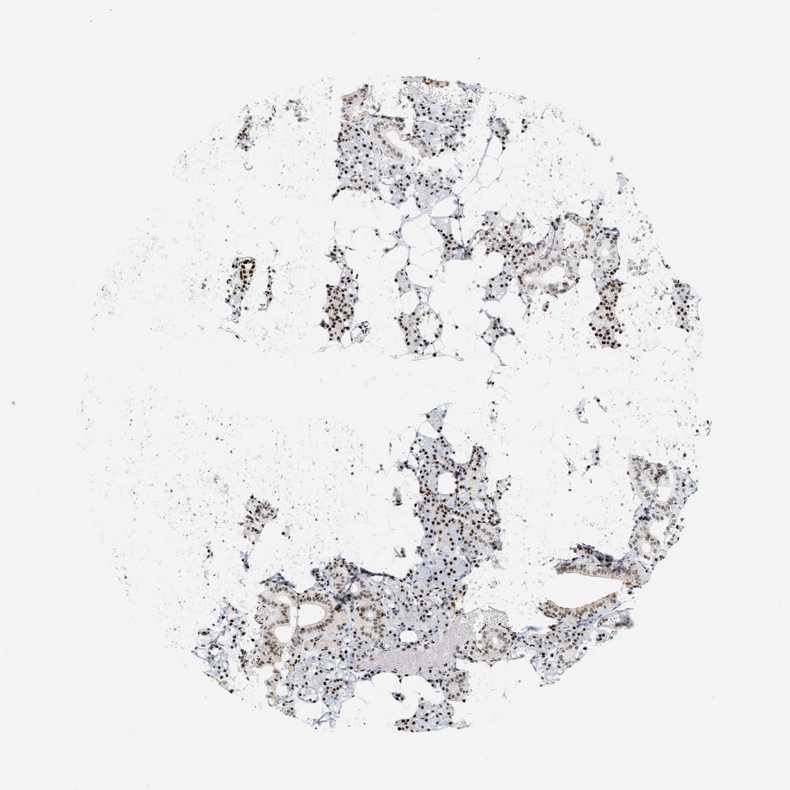

SALIVARY GLAND - Antibody stainingi

Antibody staining in the annotated cell types in the current human tissue is reported as not detected, low, medium, or high, based on conventional immunohistochemistry profiling in selected tissues. This score is based on the combination of the staining intensity and fraction of stained cells.

Each image is clickable and will lead to virtual microscopy that enables deeper exploration of all samples and also displays staining intensity scores, fraction scores and subcellular localization as well as patient and tissue information for each sample.

Antibody HPA022961Antibody HPA024457

Glandular cells HighHigh